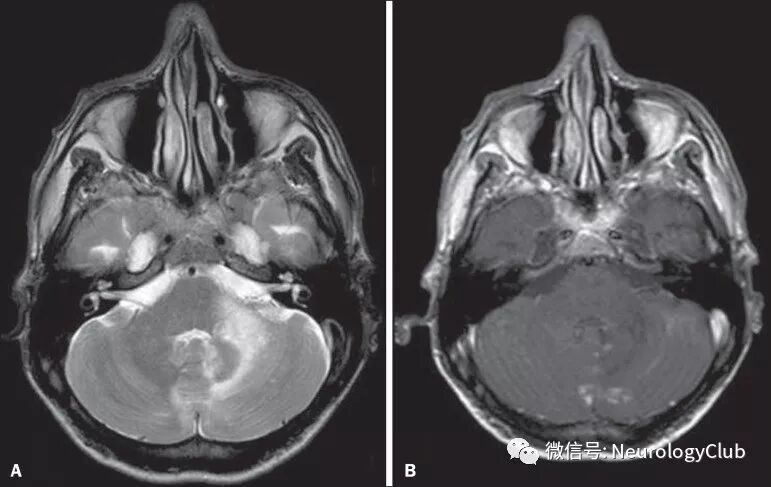

Moragas等报道的李斯特菌菱脑炎MRI异常达100%(幕下病变100%,幕上病变50%),而PNS所致菱脑炎患者MRI均正常。在病毒所致的菱脑炎中,70-75%的EV 71感染患者,50%的西尼罗河病毒感染患者,2/3合并疱疹感染患者(单纯疱疹病毒,Epstein-Barr病毒,巨细胞病毒,水痘-带状疱疹病毒和人类疱疹病毒6型)以及几乎100%的BD患者可见MRI异常信号。T2/FLAIR高信号病灶主要位于脑桥,延髓,上颈髓和小脑,而中脑累及少见。

(图3:李斯特菌菱脑炎患者;A:FLAIR可见不规则,边界不清的多发高信号病灶;B:增强T1可见左侧脑桥环形强化病灶

(图4:神经白塞病患者;FLAIR和T2WI可见双侧小脑和脑桥高信号病灶)

(图5:垂体大腺瘤放疗后患者;FLAIR和T1增强可见脑干和其与小脑交界处广泛水肿伴放疗区强化)

(图6:进行性多灶性白质脑病患者;T2WI和T1增强可见脑干和小脑边界模糊高信号病灶伴不规则强化)